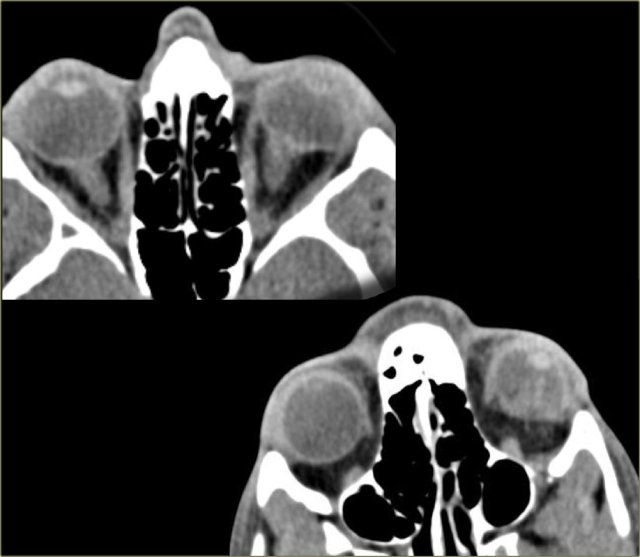

In children calcifications in the globe means retinoblastoma until proven otherwise even if it is bilateral.

On the left an image of an adolescent with bilateral retinoblastoma.

On the left images are of a 13 month old female with bilateral lesions as a result of bilateral retinoblastoma.

On the left images are of another patient with retinoblastoma.

This tumor presents as a large calcification.

When a retinoblastoma occupies more than half of the globe, as in this case, the eye has to be enucleated.